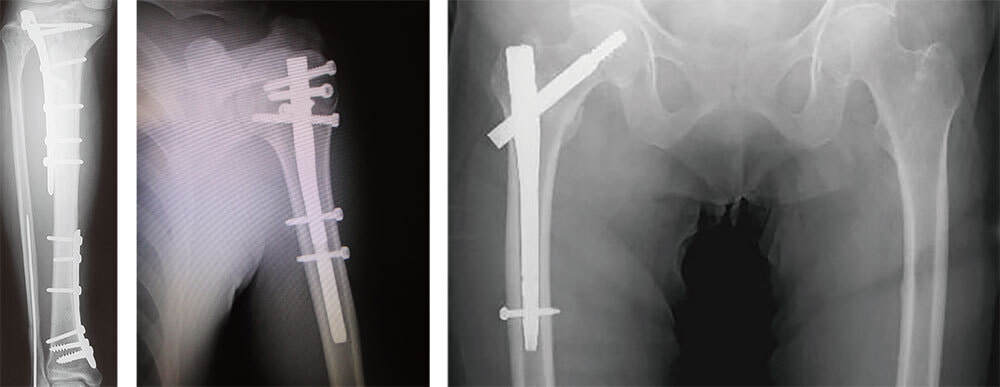

外傷センター

外傷の治療は最適なタイミングで、外傷治療に習熟した者によって的確な治療が行われて初めて、機能の最大回復を望めるリハビリテーション加療へと移行していくことが可能となります。

このような外傷の患者様が社会復帰するまでには、各時相において整形外科医が適切な加療を行うだけでなく、リハビリテーション科や地域連携室など多職種間で共働しチーム医療を充実化することによって初めて質の高い医療が提供されることになります。

当院外傷センターではこのような質の高い外傷医療を提供することを目標としています。地域の患者様や医療機関の関係者様から信頼されるよう今後も最大限に努力してまいります。

下腿骨骨折術後(左)

上腕骨頚部骨折術後(中央)

大腿骨転子部骨折術後(右)